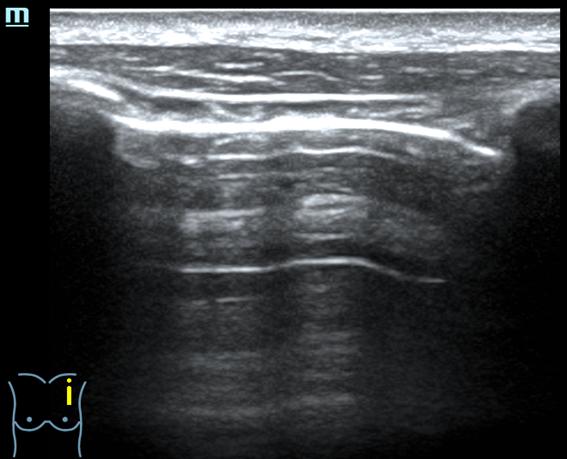

- Ecografía pulmonar (protocolo BLUE): Perfil A en los 4 puntos BLUE anteriores: deslizamiento pleural y líneas A. Signo de la playa en modo M. Puntos PLAPS: deslizamiento pleural, irregularidades pleurales, >2 líneas B.